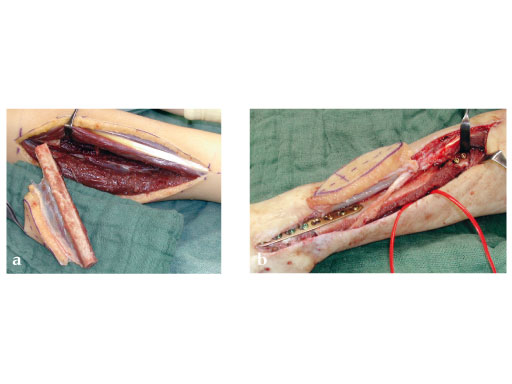

Fig 2ab: Resection of necrotic radius, temporary ExFix and pallacos spacer.

Fig 3a: Microvascular osteocutaneous free fibula flap for reconstruction of radius and dorsal skin.

Fig 3b: Proximal osteosynthesis with two screws and arthrodesis of wrist wrist with LCP 2.7.